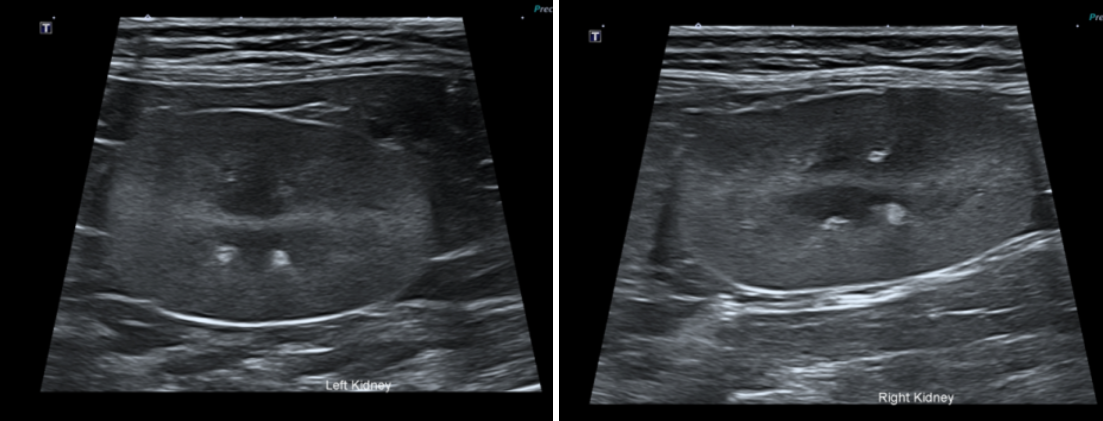

양측 신장의 퇴행성 변화 관찰되며, 신우확장 및 비뇨기 폐색 소견은 확인되지 않았습니다.